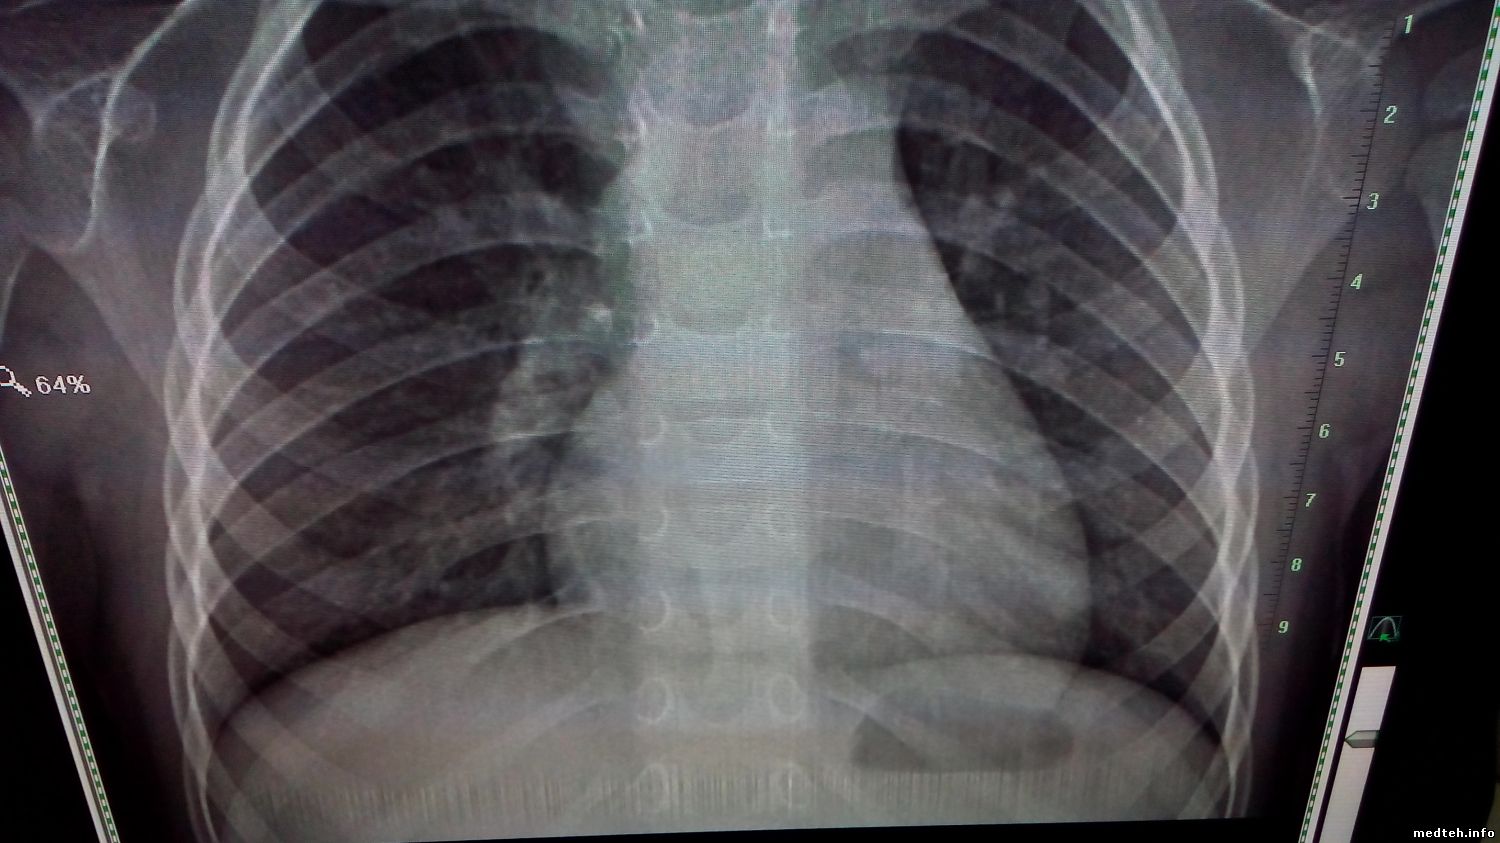

Всем добрый день, появилась проблема с КРТ Око, скопия ведет себя не стабильно (фото). При исследовании, изображение может пропасть, может быть искажено либо вообще отсутствовать.При этом аппарат не выдает никаких оошибок. С графией таких проблем нет, работает стабильно. Подскажите куда копать, насколько я понимаю, обработкой изображения занимается станция лаборанта. Спасибо.

0962386.jpg (116.6 Kb) · 7747136.jpg (76.0 Kb) · 3348363.jpg (86.6 Kb) · 4345735.jpg (135.3 Kb)